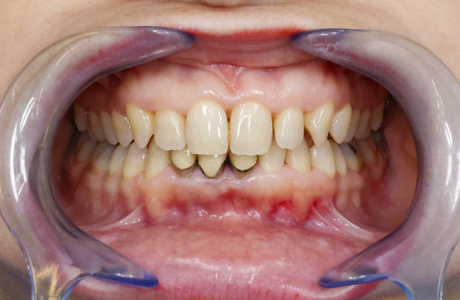

La gingivite est le premier stade de la maladie parodontale. La jonction gencive-dent est colonisée par des bactéries qui déclenchent une inflammation de la gencive. Rouge, gonflée et douloureuse, la gencive se décolle de la dent et le tartre s’accumule sous la gencive. A un stade avancé et en l’absence de traitement, la gingivite évolue en parodontite.

LA PARODONTITE

Au stade de la parodontite, la destruction porte alors sur l’os de la mâchoire et les ligaments de soutien qui ancrent les dents (ligament alvéolo dentaire). Des poches parodontales se forment et les bactéries s’y accumulent, avec plus ou moins de pus. A terme, le déchaussement de la dent peut amener la perte de celle-ci, accompagnée parfois d’une collection purulente très douloureuse.